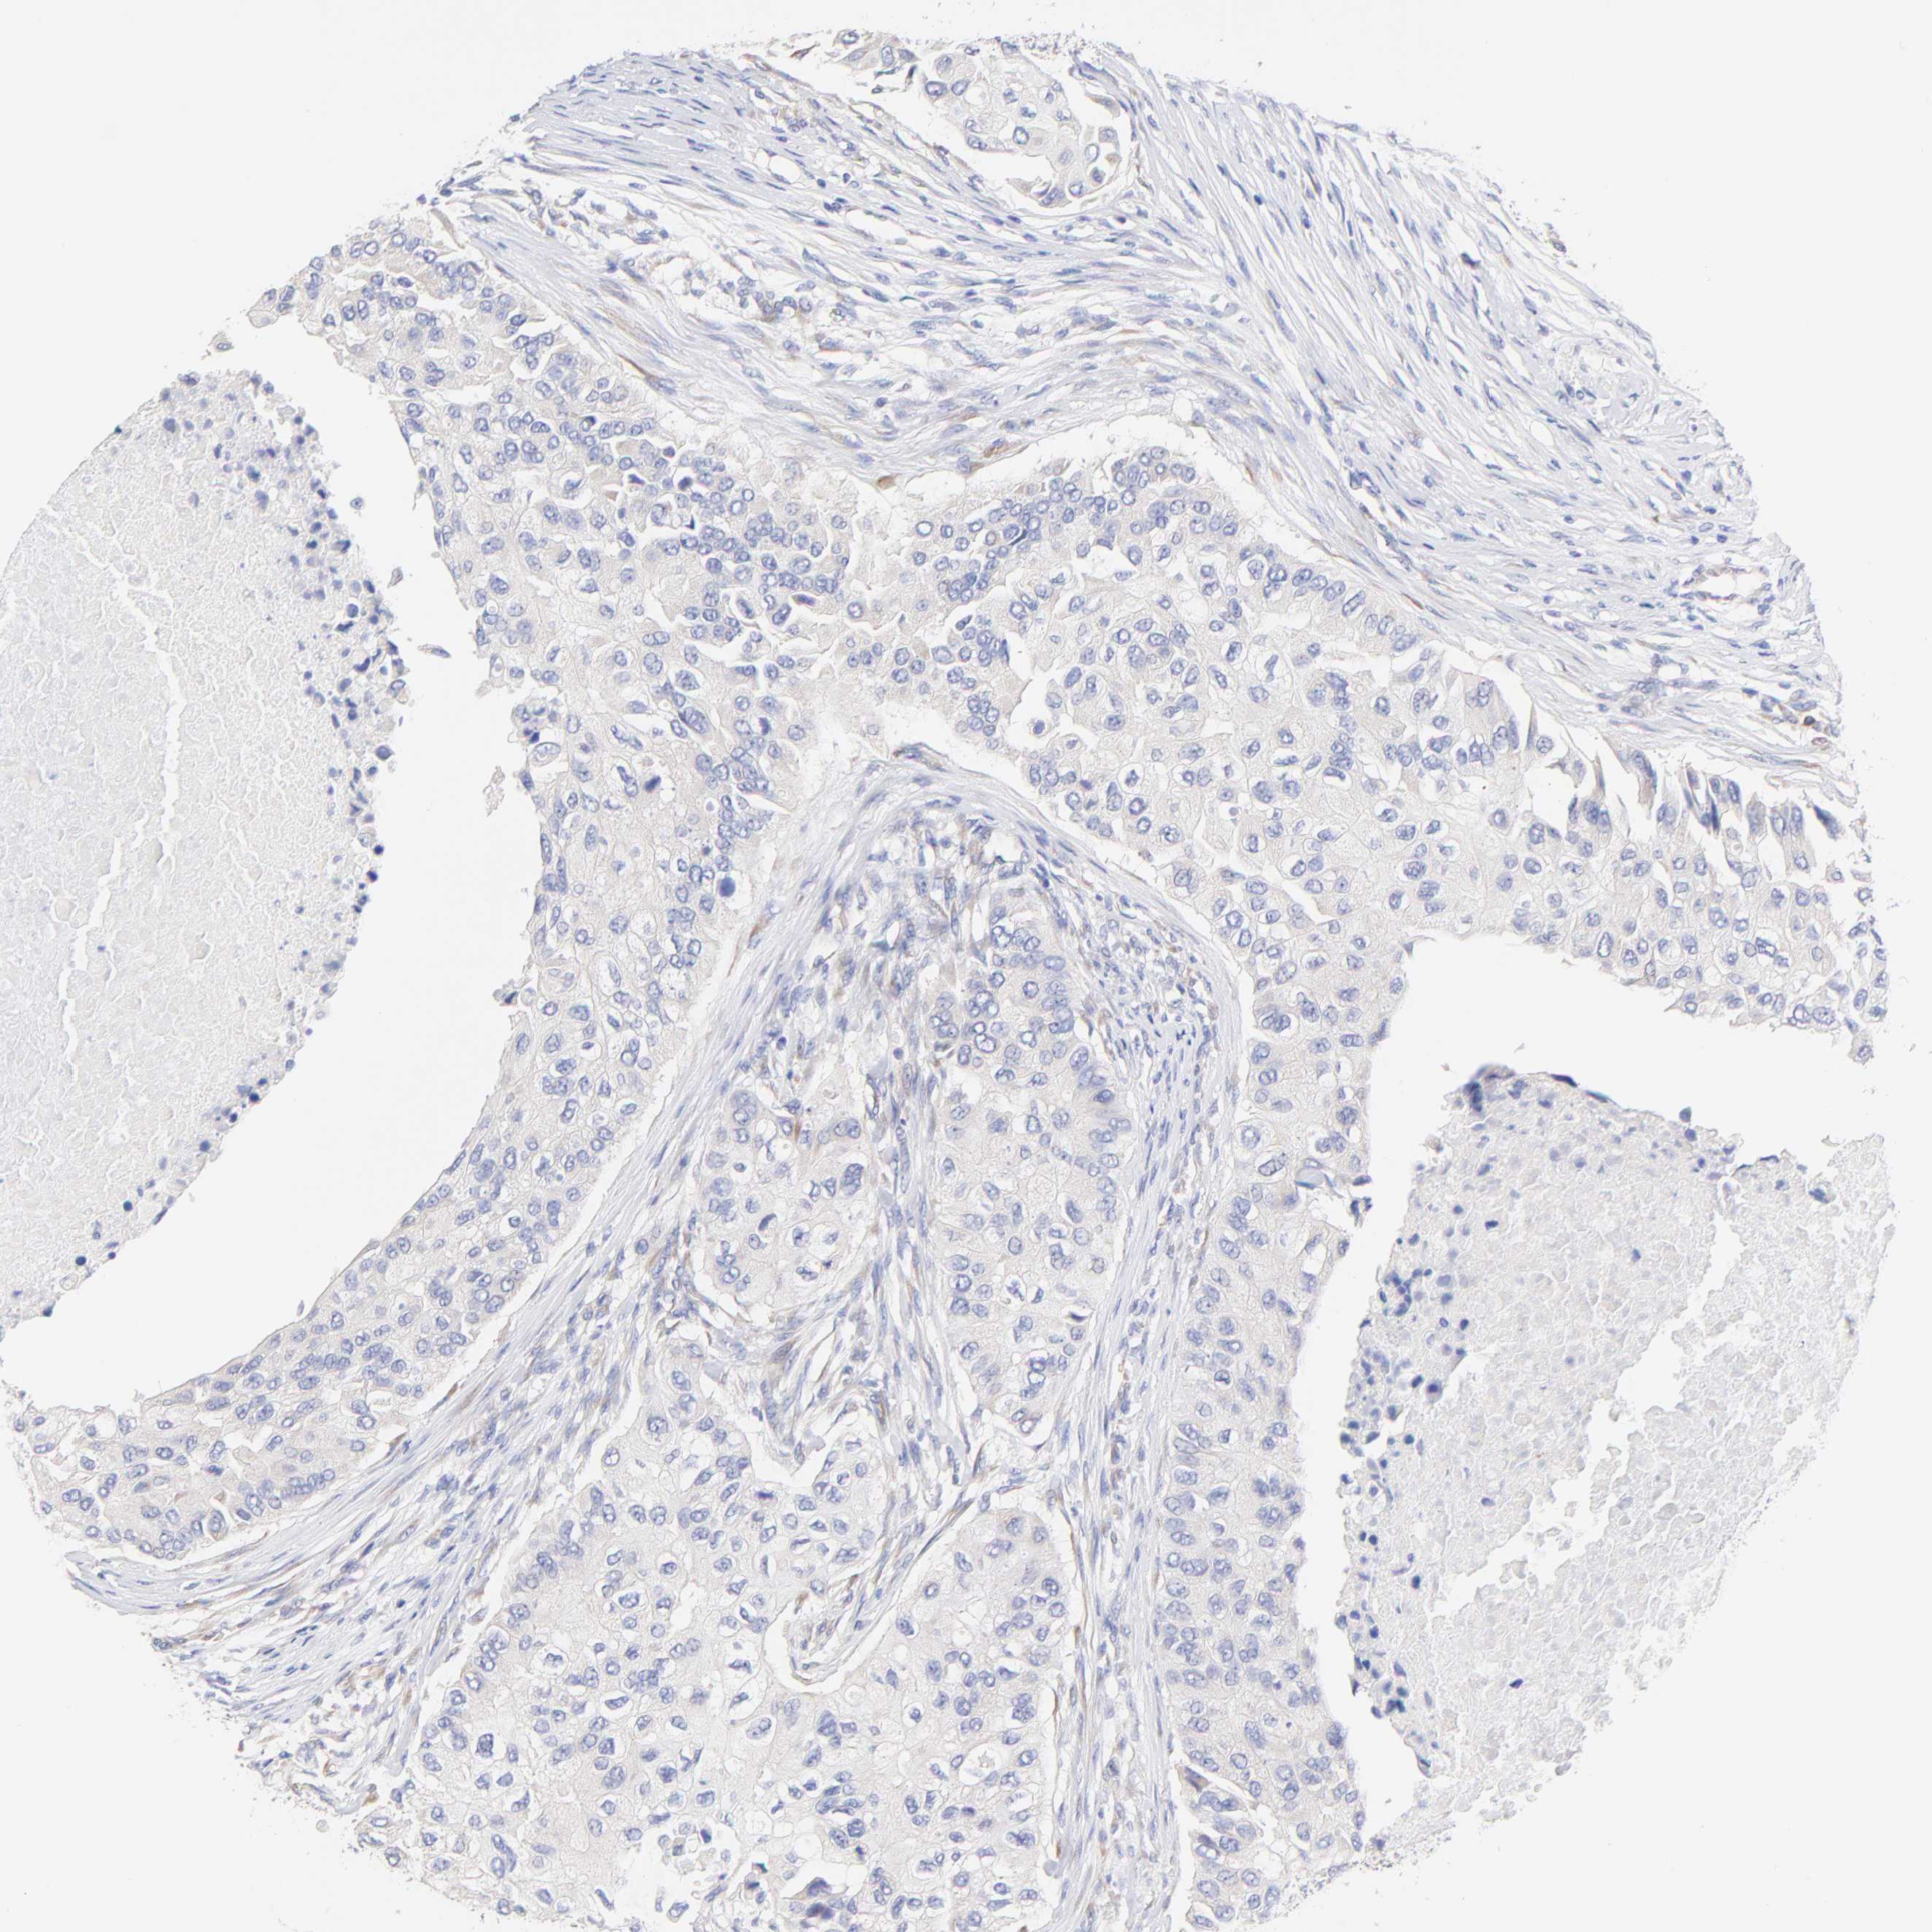

BRCA TCGA BRCA VALIDATION PROTEIN EXPRESSION

ANTIBODIES

AND

VALIDATION